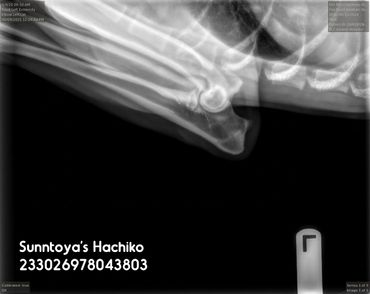

Elbows (SV): Normal

LUW (SV): 0

OCD (SV): No